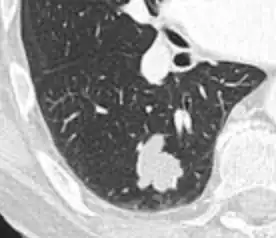

- In case of subsolid nodules, being part solid has a higher risk of cancer than being purely ground glass opacity.

-

Part solid nodule.[9] -

Ground glass opacity nodule.[9]